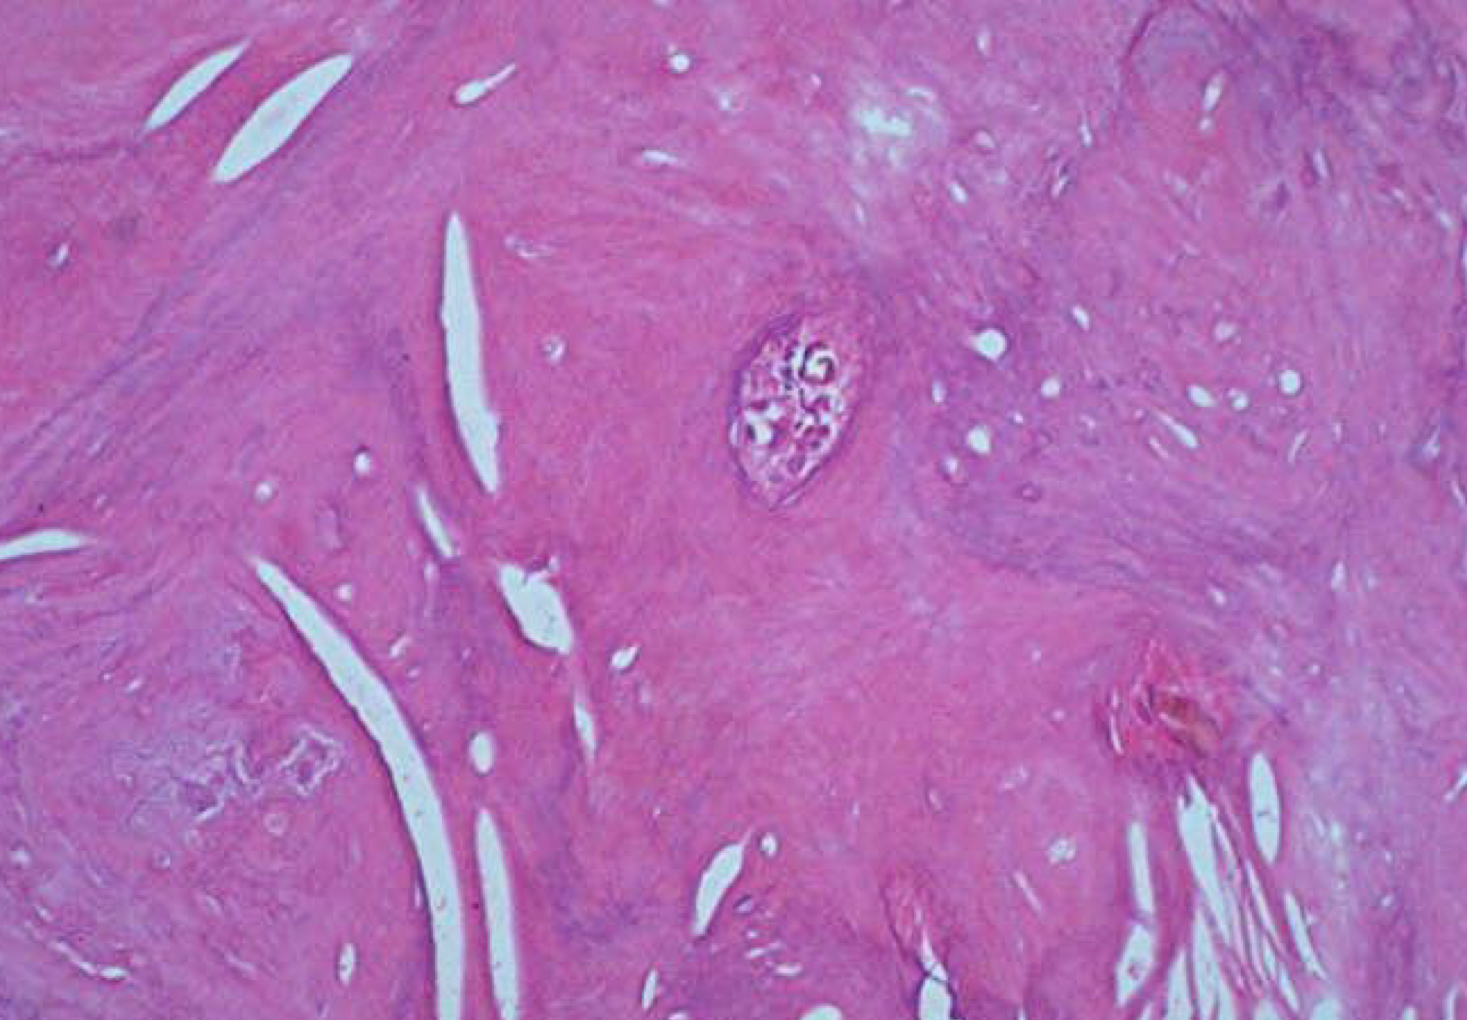

sclerotic bone = mineralized tissue vs granular tissue - less dense

condensing osteitis